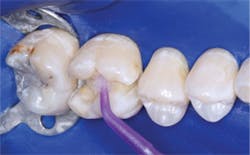

- Place glutaraldehyde solution (examples are Heraeus Kulzer Gluma, Danville MicroPrime, Clinician’s Choice G5, Centrix Glu/Sense). Optimum use according to microbiologic research at TRAC research, a nonprofit component of Clinicians Report (CR), is two 1-minute separate applications of glutaraldehyde solution, sucked off, NOT washed off. However, any use of glutaraldehyde is advantageous regardless of time of contact. Do not get the glutaraldehyde solution on the soft tissue. These solutions ARE NOT a problem when used before dentin bonding agents in spite of some companies that recommend not using them. Recent CR research has shown that glutaraldehyde solutions either do not alter the bonding values, or slightly improve the bond of bonding agents at placement and at six-month testing. More information is available in the August 2012 issue of Clinicians Report at www.cliniciansreport.org.

- Place resin-modified glass ionomer on the deepest areas of the tooth preparation, not on the margins. The material should be about 0.5 mm thick or slightly thicker. Cure it.

- Place the self-etch bonding agent of your choice. The bonding brands noted in this article have well-proven excellent results on dentin and enamel without total etching. Although when total-etch is done well it is successful, our research shows it creates significantly more unpredictable postoperative tooth sensitivity than self-etch techniques.